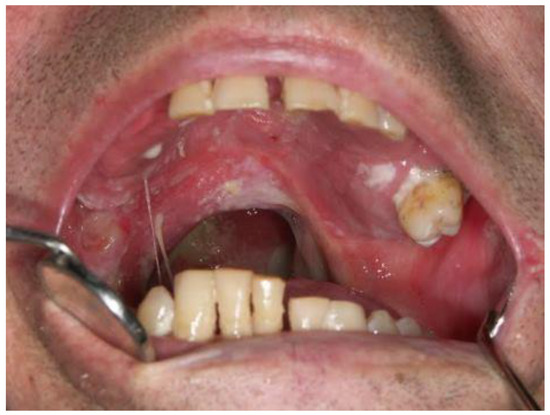

Oral Manifestations of Vitamin C Deficiency